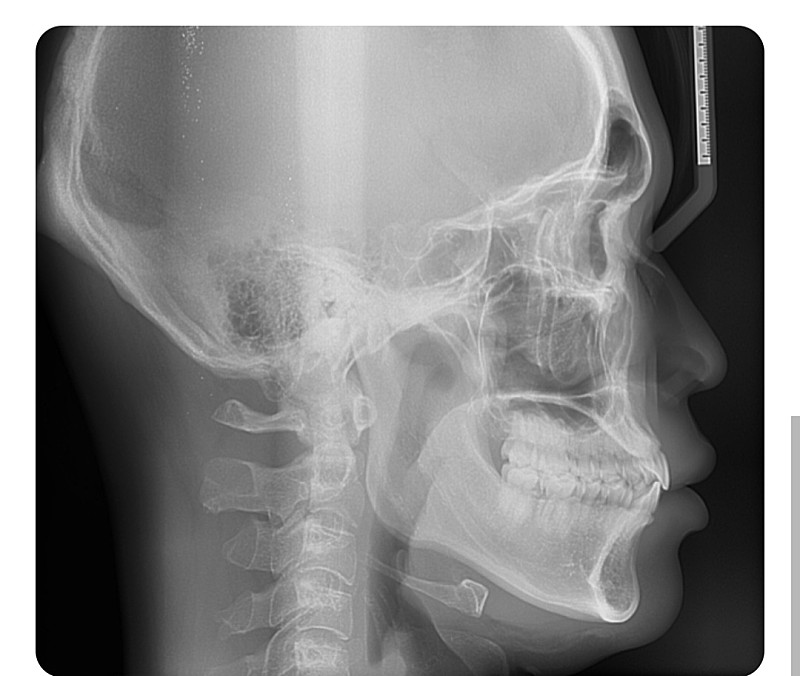

상악이 덜 발달된 것으로 보여집니다. 정확한 것은 임상사진을 통해서 연조직과의 관계도 파악해야 하며 현재 자료의 단편적인 것으로 평가하지 않습니다. 얼굴 및 신체는 3차원적이기 때문에 임상사진 및 방사선 사진 그리고 여러가지 검사 등을 통해 최종 확진하므로 치과 교정과 방문 후 상담을 해보시길 바랍니다.

하악 골격이 발달되어서 치아가 나와보이는 거나 아니면 돌출입처럼 보이는걸까요?

-하악골격이 발달되면 흔히 말하는 주걱턱처럼 보이게 됩니다. 돌출입은 치아보다는 골격적인 이유가 큽니다.

상악이나 하악이 정상범위보다 많이 발달되어있는 건가요?

-많이 발달됫다기 보다는 정상범주에서 벗어낫다고 보시는게 맞을것같습니다.

개선을 원한다면 교정만으로는 무리인가요?

-골격적으로 이상이 있다면 교정만으로는 효과를 볼수 없습니다.